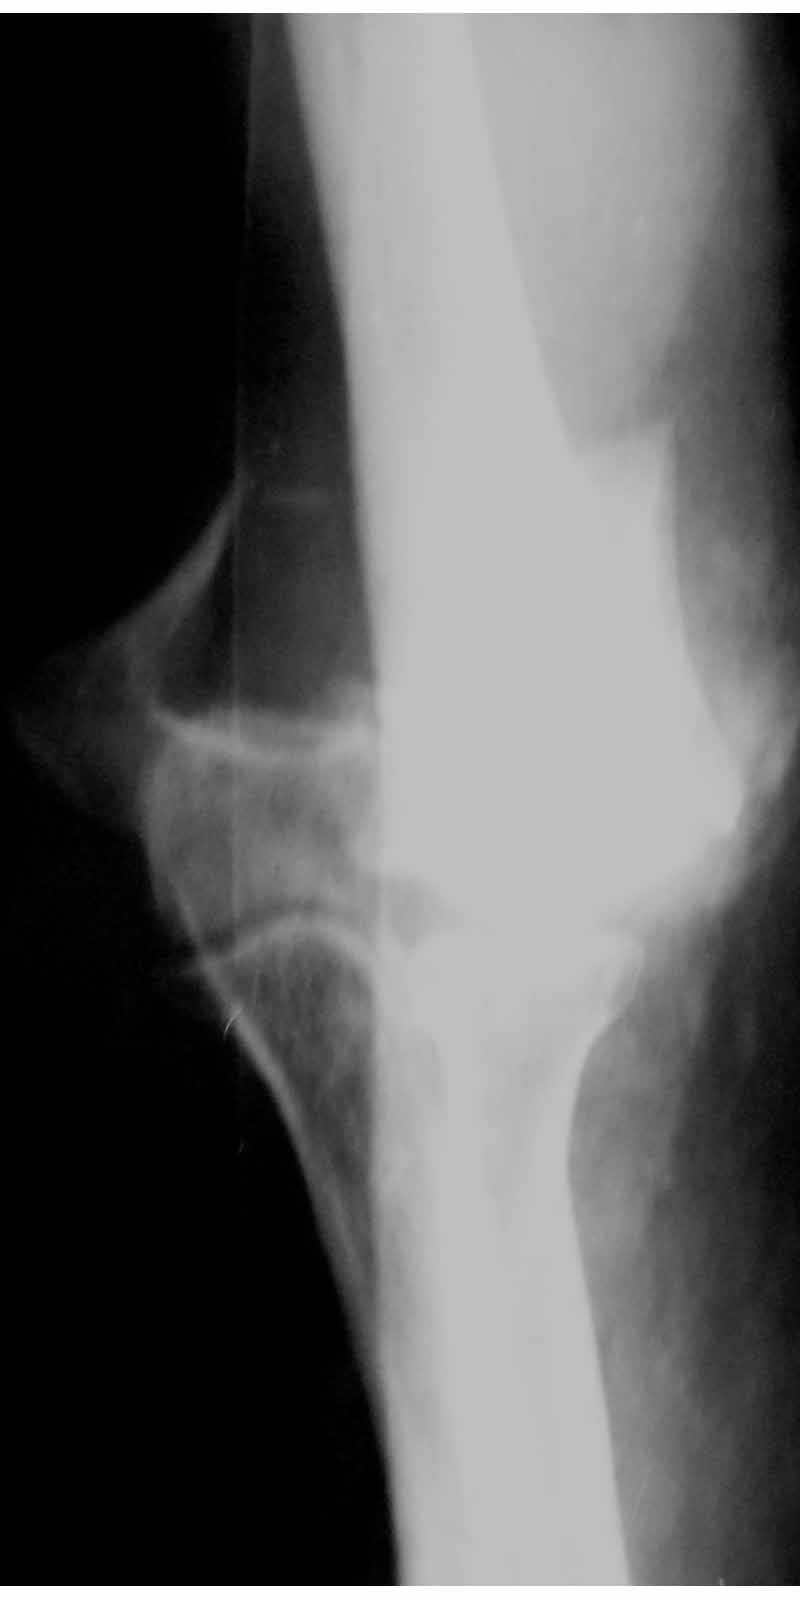

Женщина 42 лет, операция через неделю после перелома.

Д-з - открытый перелом мыщелков со смещзением и локтевой кости

без смещения - падение с лошади.

Остеосинтез закрытый (если так можно выразиться), т.е. без

разрезов. Длительность операции - около 1,5 часа со студентом.

6 щелчков ЭОПом.